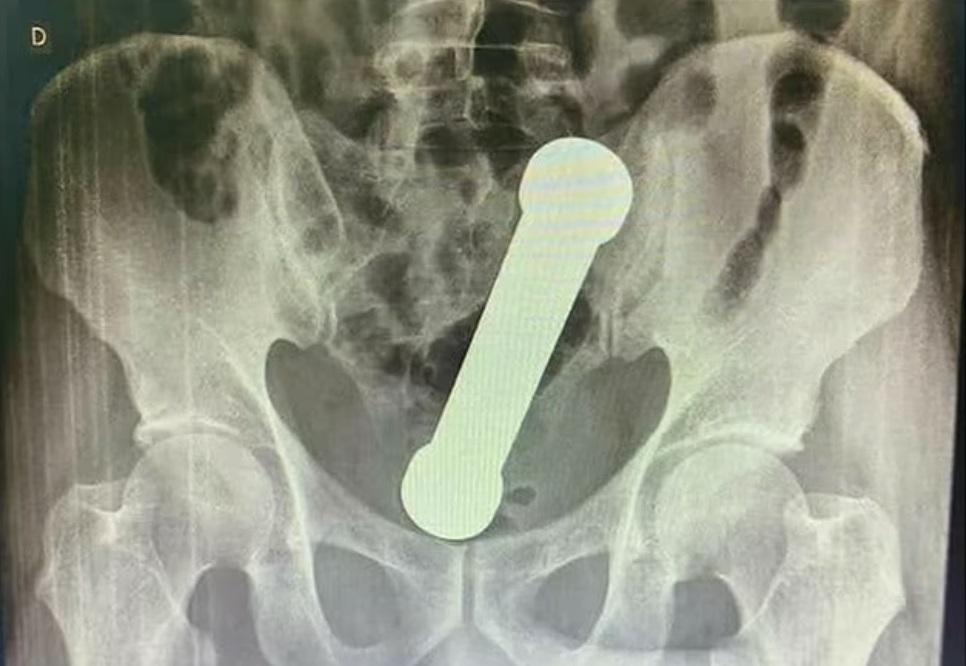

X光檢查顯示啞鈴的位置。(互聯網)

英國《每日郵報》報道,該名54歲男子把一個重2公斤、長20厘米的啞鈴塞進肛門後,發現無法取出,待了兩天後到Manaus一間醫院求醫,說腹痛、噁心、不能排便。報道指,醫生說該名男子在檢查時不合作,經X光檢查後發現,一個20厘米長的啞鈴卡在結腸與直腸連接的位置。

醫療團隊近日在《國際外科案例報告期刊》(International Journal of Surgery Case Reports)公布這個案例,指手術難度很高,但最終成功,男子留醫3日後出院。